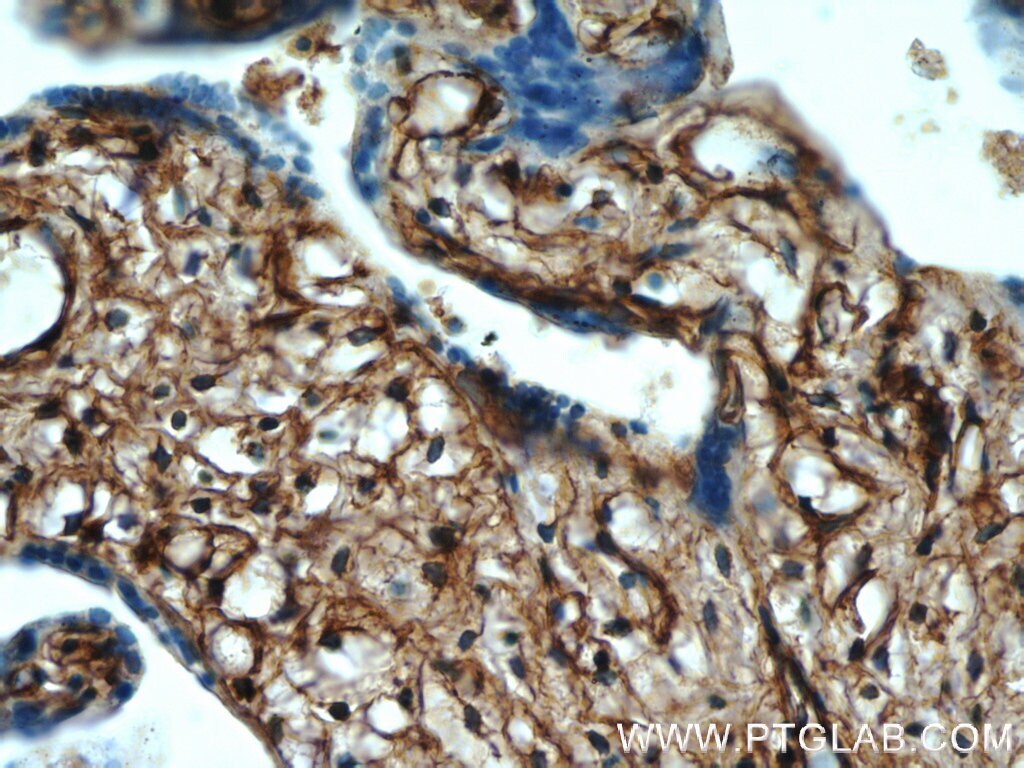

- Submitted by

- Invitrogen Antibodies (provider)

- Main image

- Experimental details

- Immunohistochemistry of paraffin-embedded human placenta tissue slide using 22522-1-AP ( HPGDS antibody at dilution of 1:50 (under 40x lens).